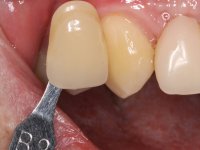

O paciente foi observado conjuntamente e a dúvida que surgiu de imediato foi se seria possível com a regeneração óssea a efectuar poder ser reabilitada naturalmente a zona das papilas interdentárias. Nesse sentido foi feito um enceramento de diagnóstico que contemplaria as duas hipóteses, utilizando ou não a cerâmica gengival. A confecção desse enceramento foi fundamental para expor ao paciente a dificuldade da reabilitação. O wax-up deu origem a um mock-up que foi aprovado pelo paciente e que simultaneamente serviu de guia imagiológica. O caso foi planificado cirurgicamente e realizada uma guia cirúrgica com que foram colocados os implantes. Após 10 semanas foi feita a 1ª impressão para confecção da ponte provisória. Foram criados os primeiros perfis de emergência na gengiva artificial e foi digitalizado o modelo. Por processo de CAD-CAM foi confeccionada uma ponte provisória aparafusada baseada no enceramento de diagnóstico. A ponte trabalhou durante 8 semanas os tecidos moles que foram fielmente copiados numa impressão com técnica de moldeira aberta. Os transferes foram individualizados com resina composta para copiarem fielmente os perfis de emergência criados pela ponte provisória. Confeccionado o modelo de trabalho definitivo, foi realizada uma infra-estrutura em zircónio seguindo a orientação do enceramento de diagnóstico. O assentamento da infra-estrutura foi testado em boca e simultaneamente foi novamente impressionados os tecidos moles com um silicone fluido. Nessa consulta foi feito o levantamento da cor. Os dentes 13 e 23 apresentavam uma saturação anormalmente forte que resolvemos não valorizar, optando por privilegiar a relação com o sector antero-inferior. Foi realizada uma nova gengiva artificial com a impressão que acompanhou a impressão de arrasto com a infra-estrutura. Após a colocação da cerâmica na infra-estrutura foram coladas as meso-estruturas. O trabalho final foi aparafusado lentamente permitindo a adaptação dos tecidos moles.